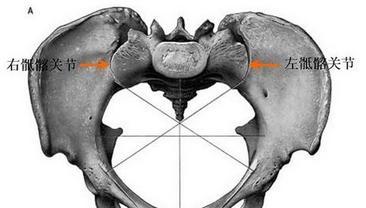

ca69c7189f9857e58a54068013965fe9.jpg

(圖:骶髂關(guān)節(jié)具體位置如圖所示)